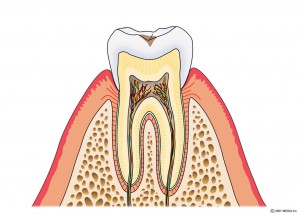

エナメル質に達するむし歯

光重合レジン充填・他

象牙質に達するむし歯

光重合レジン充填・部分的な詰め物(型どりを要す物)

歯髄に達するむし歯

歯の神経を取ります→土台を立てます→被せものをつくります。

CO:初期むし歯

C1:エナメル質に達するむし歯

C2:象牙質に達するむし歯

C3:歯髄に達するむし歯